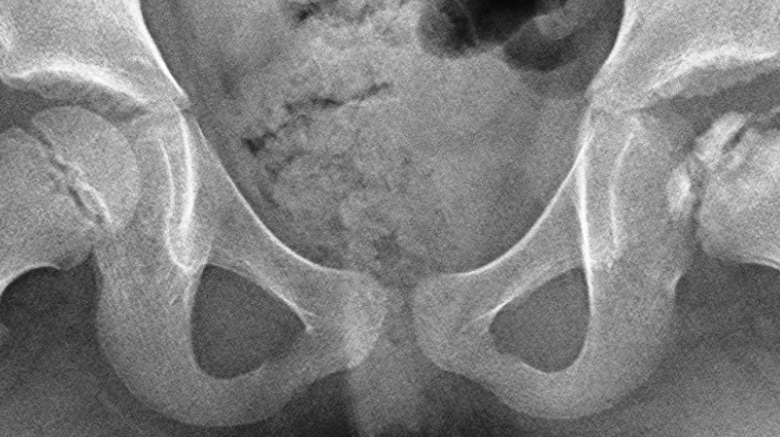

Radiografía (aunque en los primeros RX puede no manifestarse).

Tras la necrosis, la cabeza del fémur se aplana, después el hueso se fragmenta y posteriormente comienza la regeneración.

El suministro de sangre retorna en varios meses produciendo osteocitos nuevos, los cuales gradualmente reemplazan el hueso muerto y la cabeza del fémur comienza a formarse otra vez.